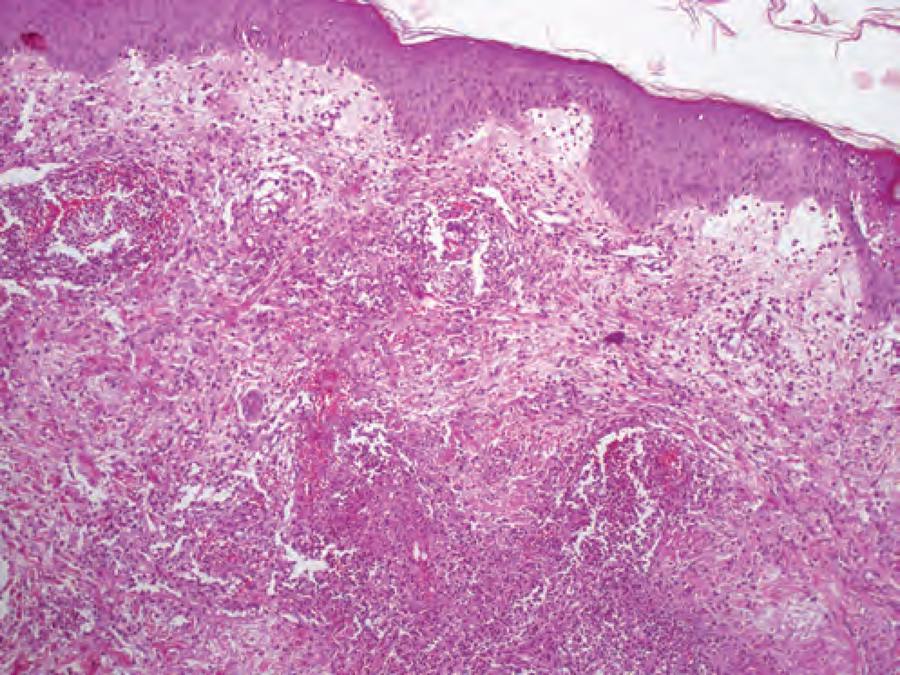

73-year-old male with past medical history of ESRD on hemodialysis secondary to ANCA vasculitis presented with sudden onset of nodular/ bullous hemorrhagic lesions that initially erupted at the back of neck gradually progressed to face, head and upper torso. On admission, patient also complained of photophobia and fatigue. In the past, he reportedly had hives after radioiodine contrast use. A week prior to presentation, he was diagnosed with ascending colitis on CT abdomen w/ contrast, which resolved with ciprofloxacin and metronidazole, confirmed by a repeat CT abdomen w/ contrast before discharge. Work up on the current presentation was significant for leukocytosis of 12000, neutrophilia of 10400, thrombocytopenia, erythrocyte sedimentation rate of 33 and CRP of 18.1. Biopsy of the skin lesion revealed a diffuse infiltrate of neutrophils with prominent edema in the superficial reticular as well as papillary dermis, indicative of acute febrile neutrophilic dermatosis. The skin lesions resolved with 40mg of prednisone.

Discussion: Sweet syndrome can be divided into classical, malignancy-associated and drug-induced sweet syndrome. Our case was a rare bullous variant of sweet syndrome secondary to underlying IV contrast use. Bullous variants have been reported in hematological malignancies, but not in relation to drugs, especially never with IV contrast use (1). Our patient met all the criteria for drug-induced sweet syndrome except fever. Criteria include, abrupt onset of painful erythematous plaques and nodules; histopathological evidence of a dense neutrophilic infiltrate without leukocytoclastic vasculitis; temporal relationship with drug use and clinical presentation with resolution of symptoms after steroid treatment. This disorder mainly affects 30-70 age group and reportedly has a female predominance. Pathogenicity is due to cytokine dysregulation. There are theories about elevated blood G-CSF levels, which are known for prolonging survival rates of neutrophils, eventually resulting in increased oxidative metabolite production, chemotaxis and phagocytosis(2). Elevated G-CSF are also found in ANCA vasculitis, which makes patients more susceptible to developing Sweet syndrome in the presence of triggers like radioiodine contrast.